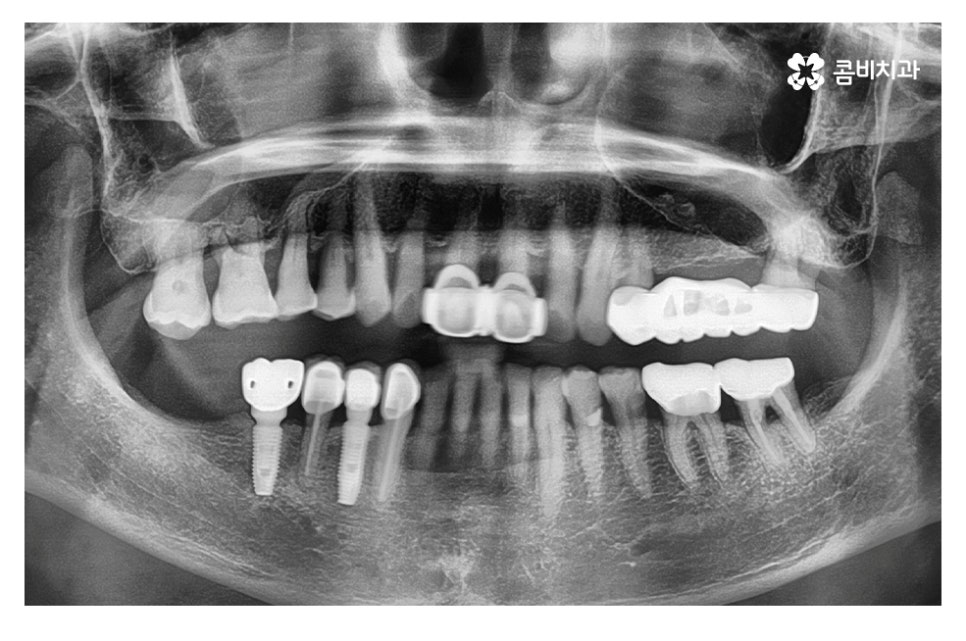

위 케이스의 경우 영구치가 손실된 상태에서 시간이

어느 정도 경과된 후 임플란트 수술을 진행하였으며,

영구치가 손실되고 어느 정도 뼈가 차있고, 현 상태에서

식립이 가능했기 때문에 뼈이식 없이 임플란트를 식립하였고

이때 골 유착 과정을 거치면서 임플란트가 단단하게 고정되고

치료가 마무리되면 자연치아에 버금가는 저작력을 갖추게 될 수 있어요.